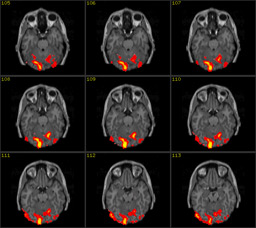

The illustration shows two images: the first one is a scan of the brain

obtained with Magnetic Resonance Imaging (MRI), the second is its functional

version (fMRI). MRI is a non-invasive scientific technique that generates

images of the body for diagnostic and research purposes. Along with its

functional version, MRI has been extensively applied to studies of brain

anatomy and cognitive functions, enabling researchers to detect and measure

the neuronal activity in almost real time. By showing the human brain at work,

brain scans are presented in the wider public arena and, specially, in the

media, as evidence of conditions of normality or illness that prompt us to

reshape our concept of personal identity (Dumit 2004).14

This series of images can be seen but cannot be read without knowing the language of neuroscience and of brain anatomy and physiology. For the purpose of this essay, it is not worthwhile going into details on how brain scans are produced, re-mediated and interpreted inside and outside the laboratory. Therefore, I shall not discuss the scholarly literature (de Rijcke and Beaulieu, 2014; Prasad, 2005; Alac, 2008; Dumit, 2004 to name just a few) that shows how brain images are the result of complex socio, technical and semiotic procedures of mediations and interpretation taking place inside the laboratory and among different professionals.